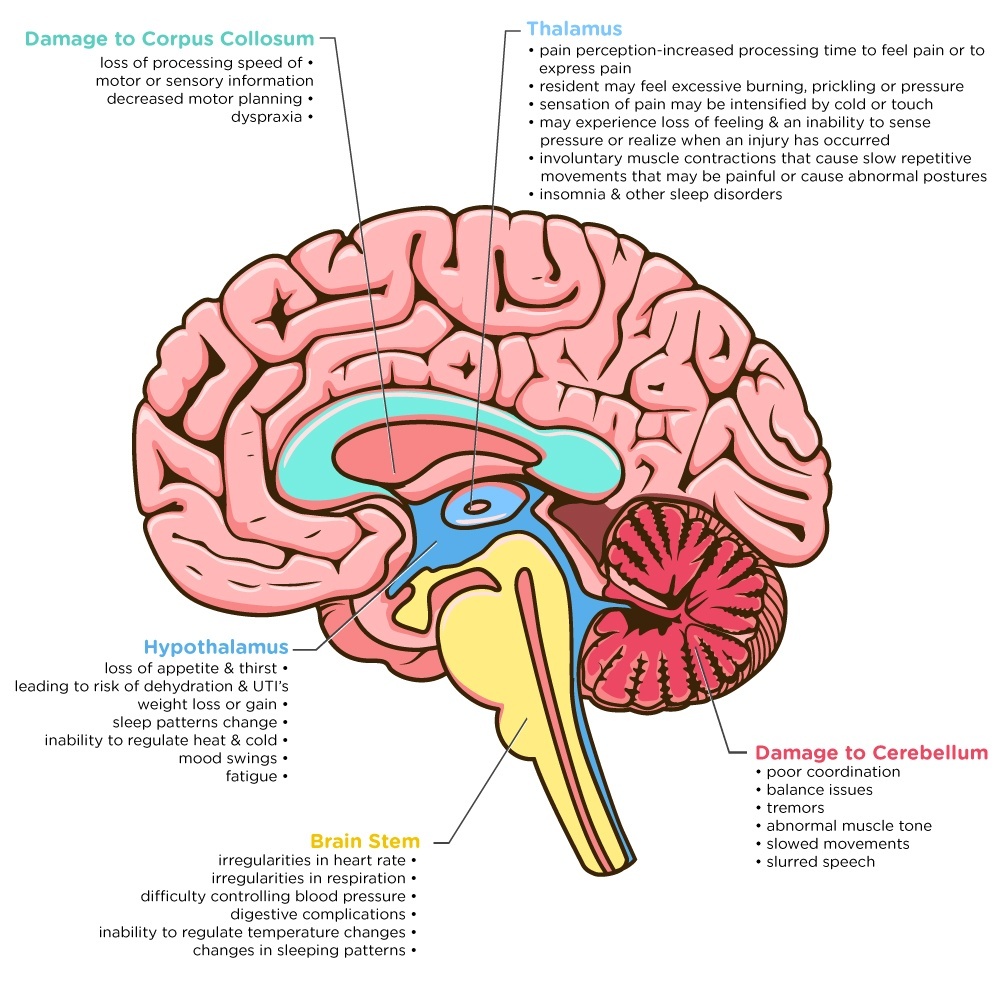

Neurosurgeons can't alter the primary injury suffered by the brain or spinal cord, but they can prevent secondary damage from occurring. The damage can be focal (confined to one area of the brain) or diffuse (happens in more. For severe tbis, treatment may include medication, surgery, and rehabilitation.

Aphasia is most often caused by damage to areas of the brain that play a role in speech and language. Learn more about brain injury the first step when caring for someone with brain injury is to learn more about their specific condition. Always see your doctor if you or your child has received a blow to the head or body that concerns you or causes behavioral changes.

Treatment treatment is based on the severity of the injury. The need for imaging is based on a physical examination by a doctor and a person's symptoms. While there is no standard treatment for reversing brain damage, there are a few different therapies that have demonstrated efficacy in a handful of patients.

When to see a doctor. The specifics of treatment, including the type, setting, and length, depend on how severe the injury is and the area of the brain that was injured. Traumatic brain injury symptoms vary depending on whether a tbi is mild or moderate and/or severe.